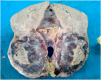

With about 110 cases reported in literature, juxtaglomerular cell tumors are rare. We report a 25 years old patient who was admitted in neurology for a hemorrhagic stroke secondary to a cerebral aneurysm rupture due to high blood pressure. Etiological investigations showed a solid mass of the left kidney. A radical nephrectomy was realized and pathological examination and immunohistochemical profile concluded to juxtaglomerular cell tumor. The originality of this observation is based on the mode of presentation of a rare renal tumor by a malignant high blood pressure.